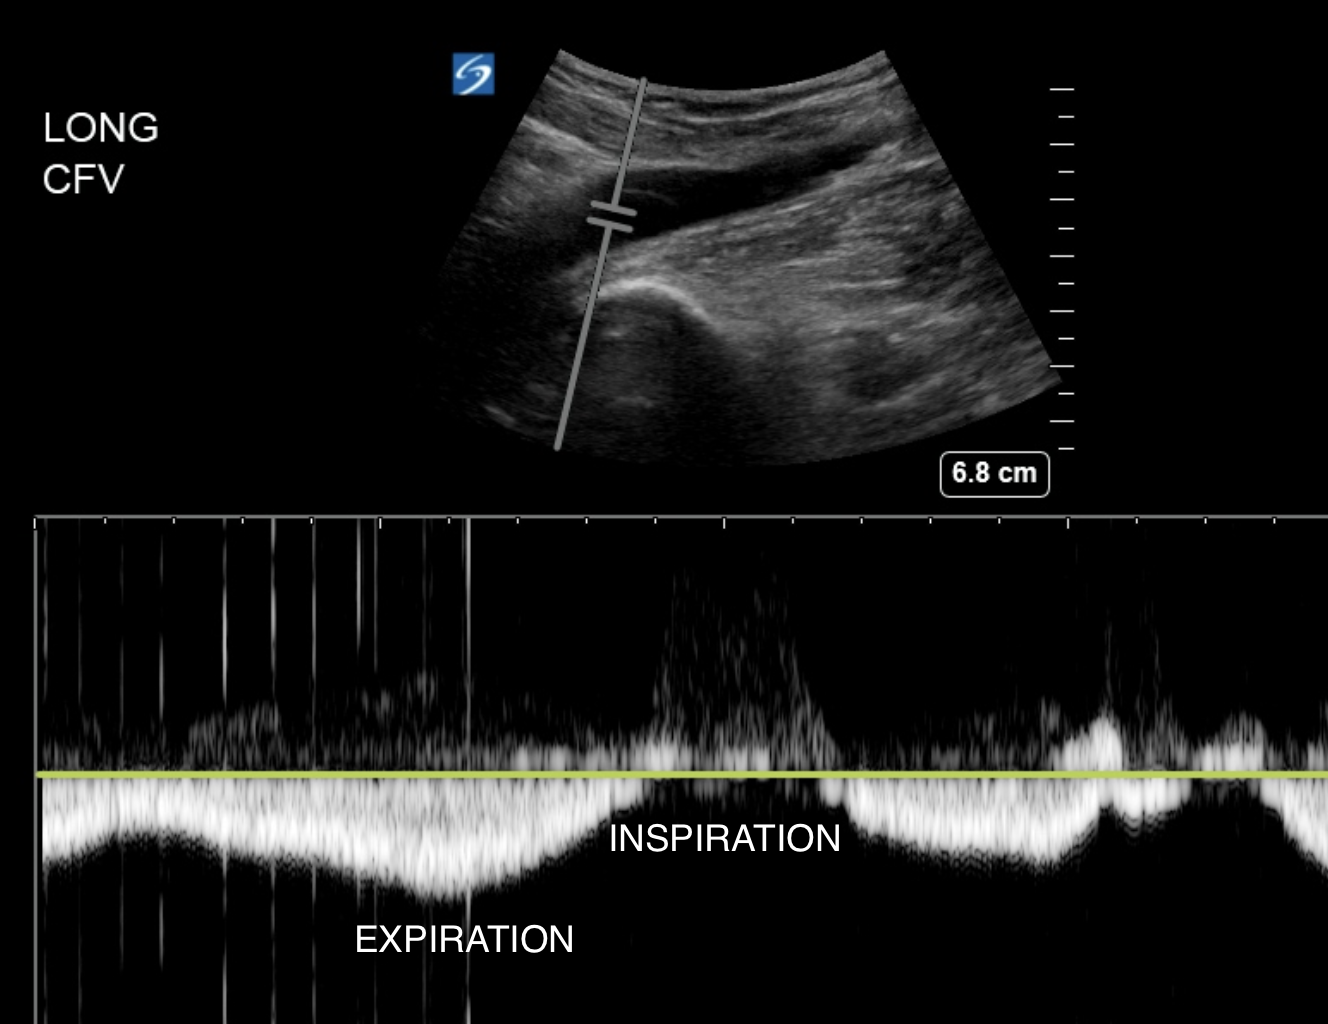

Some people also look for augmentation. This is where you image a longitudinal view of the the CFV and place the PW doppler gate in its lumen. You will see venous flow as a continuous wave

Manual compression of the calf while doing this will increase venous return and lead to enhanced flow at the time of calf compression.

Normal augmentation of flow in the CFV due to calf compression

If the proximal veins are patent, but there is a calf DVT, augmentation won't happen or will be blunted. But the usefulness of this is questionable (4).

Another thing people do is look for respiratory variation. The CFV joins the central veins: external iliac and common iliac. Central veins show respiratory variation in flow due to the variation in right heart filling with respiration. On inspiration, venous blood is pulled into the right heart. So flow diminishes on patient inspiration in the CFV if the veins are patent up to the right atrium.